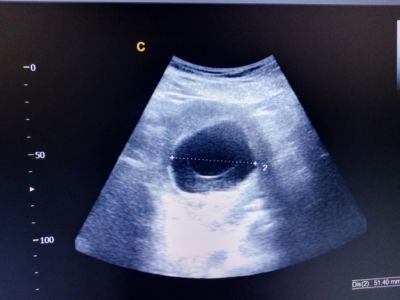

البويضة الفارغة: الأعراض، الأسباب والعلاج